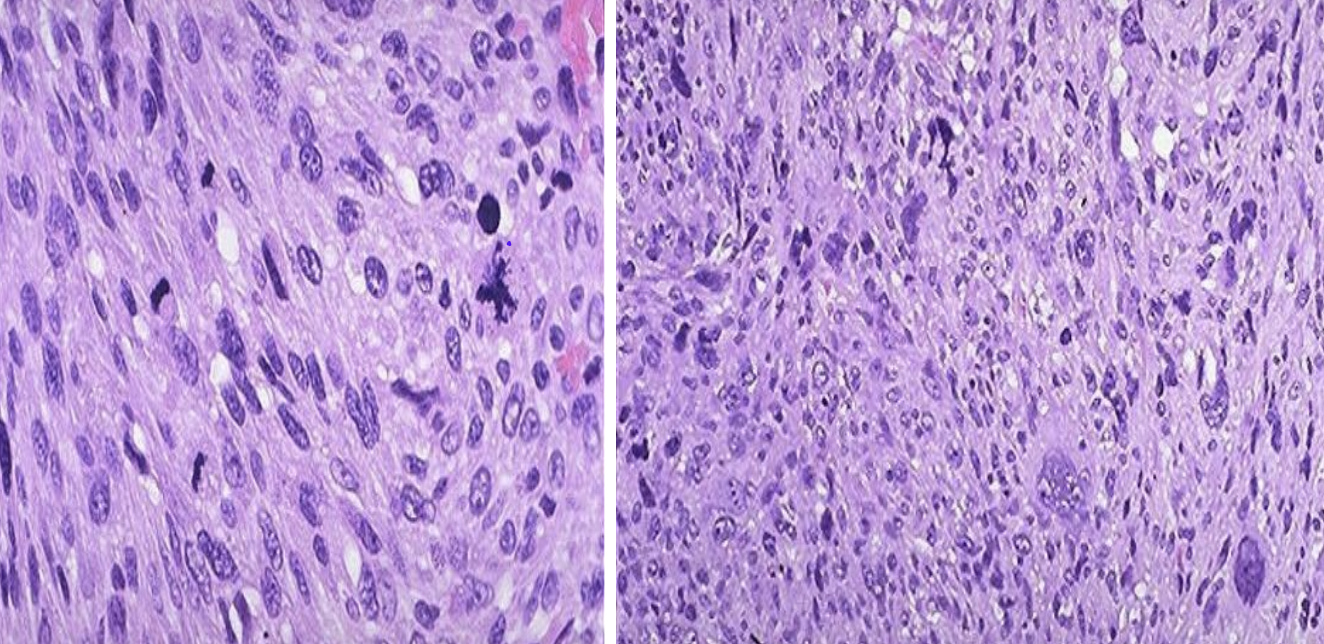

Identify the organ and the diagnosis in this format: diagnosis, organ

leiomyosarcoma, uterus